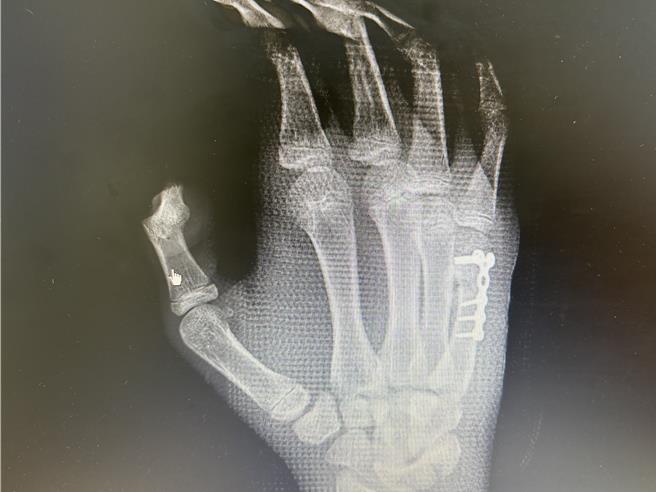

医师透过钢板固定,让国中生手掌顺利恢復。(中正脊椎骨科提供/任义宇高雄传真)

该国中生因移位角度较大,经廖志祥透过手术植入钢板将掌骨恢復到正确位置,目前已顺利復原,廖志祥提醒,运动前确实做好热身及伸展,穿戴适当的绷带、贴扎、手套等保护装备,可减少受伤,另外运动时要遵循正确拳击技巧及姿势,最后如果不幸受伤了,要及时处理及治疗。